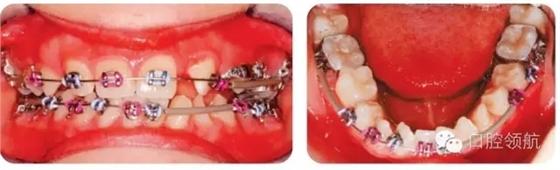

圖2.24中為何下頜有的牙齒未粘結(jié)托槽?

圖2.24

圖2.25中使用的是什么矯治方法?

圖2.25

● 0.018不銹鋼圓絲。

● 上頜右側(cè)用推簧推出前磨牙間隙。

● 前磨牙舌側(cè)粘結(jié)舌鈕,用橡皮鏈改扭轉(zhuǎn)。

● 橡皮鏈通過腭側(cè)的連接桿連接至UL6、UL5和UL4,加強(qiáng)固位。

● UL1、UR1和UR2連扎為一體,用橡皮鏈牽引UL2至正位,鄰接UL1,為UL3提供位置。